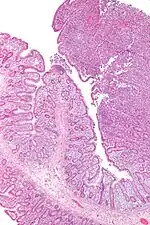

Micrograph of an enteropathy-associated T-cell lymphoma (upper right of image), a type of T-cell lymphoma. H&E stain.